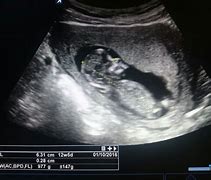

U ozbiljnom propustu koji je potresao medicinsku zajednicu, žena iz Brisbanea rodila je dijete drugog para nakon što je došlo do zamjene embriona u klinici za vantjelesnu oplodnju Monaš IVF, prenosi The Guardian.

Interna istraga pokazala je da je embrion drugog para pacijenata greškom odmrznut i implantiran ovoj ženi, čime je došlo do rođenja djeteta koje genetski ne pripada majci koja ga je nosila.